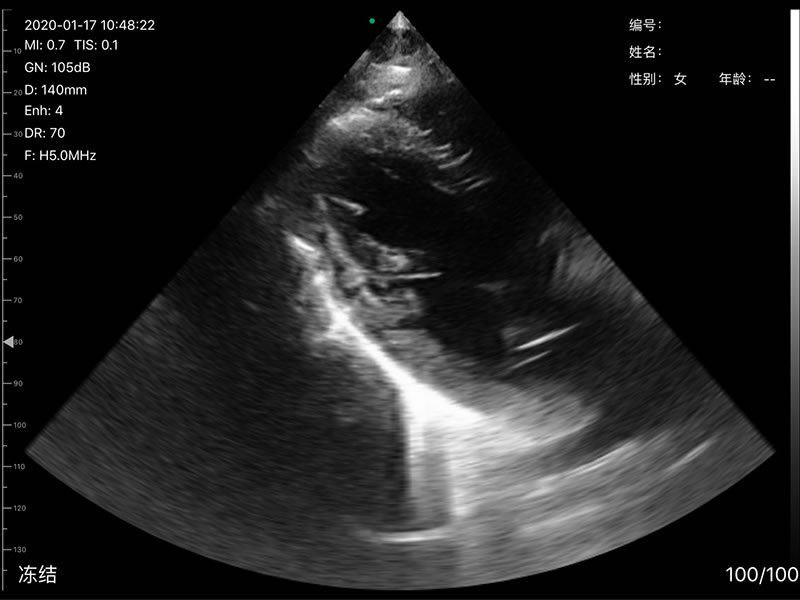

• Frequency: R60 Convex/Phasedarray probe 3.2MHz/5MHz,

• Scan angle and width: convex 60°, Phasedarray 80°, linear 40mm